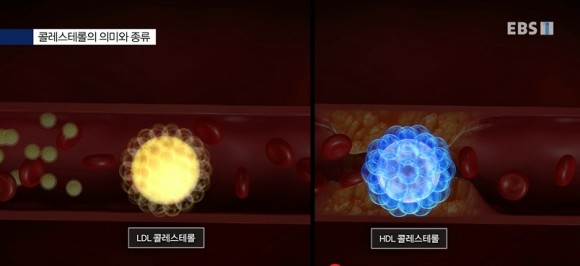

HDL: 좋은 콜레스테롤 수치가 높아야 합니다.LDL: 동맥경화를 일으킨 나쁜 콜레스테롤, 수치가 낮을수록 좋습니다.고지혈증은 LDL과 중성지방 수치가 높은 경우를 말합니다.

LDL: 간에서 만든 콜레스테롤을 쌓아 혈액을 따라 조직으로 옮기는데 이때 혈액 속에 콜레스테롤이 너무 많으면 혈관 벽에 스며들어 혈관이 좁아지는 동맥경화가 나타나게 됩니다.

HDL: 혈관 벽에 쌓인 콜레스테롤을 쌓아 간으로 이동하는 혈관 청소부 역할을 합니다.

콜레스테롤의 의미와 종류